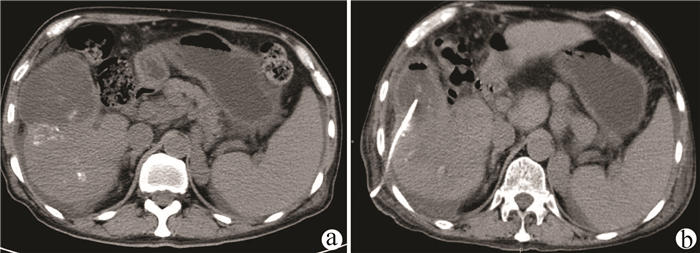

A case of hepatic angiosarcoma with Kasabach-Merritt syndrome

Mengnan LI, Gongchen WANG, Zhiming ZHANG

2021, 37(11): 2646-2648. DOI: 10.3969/j.issn.1001-5256.2021.11.032

Abstract(840) HTML (320) PDF (2149KB)(67)

Abstract: